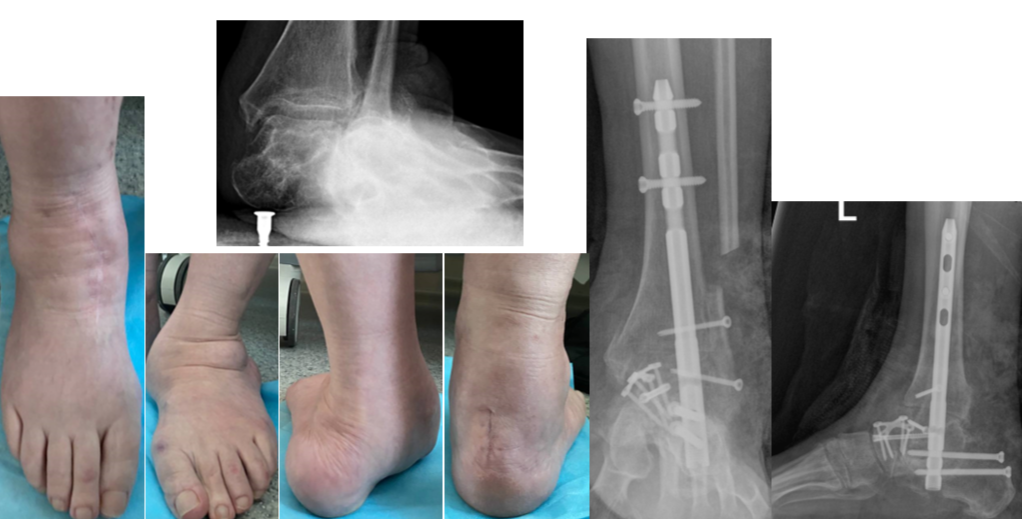

У пациентки — запущенная плосковальгусная деформация обеих стоп. Ступни были сильно «завалены» внутрь, суставы смещены. Наиболее частой причиной развития такого состояния является врождённая слабость связочного аппарата. К этому могут привести и последствия травм, неврологические проблемы. А внешние факторы — лишний вес, неудобная обувь, нагрузки — выступают как мощные провокаторы, которые резко ускоряют развитие деформации на фоне предрасположенности.

Раньше лечение Ирины Чубич было консервативным — пациентка носила ортопедическую обувь и стельки. Но, как объясняют специалисты травматолого-ортопедического отделения №6 Новосибирского НИИТО им. Я.Л. Цивьяна, на данной стадии проблема уже анатомическая — кости стоят неправильно. Исправить это можно было только хирургически.

Около года назад операция была проведена на правой ноге (более деформированной), а в феврале 2026 года — на левой.

«Сначала мы оперируем более поражённую ногу: таков стандарт безопасности. Затем требуется хирургическая пауза, чтобы пациентка восстановилась, научилась ходить на костылях, опираясь на здоровую ногу. Только когда первая стопа уже может служить надёжной опорой, мы оперируем вторую. Это минимизирует риски и делает реабилитацию комфортнее.

В обоих случаях выполняется реконструктивная операция: мы вернули стопе правильное положение и зафиксировали кости при помощи специальных конструкций, чтобы они срослись в нужной позиции»,

— комментирует к.м.н., заведующий отделением Сергей Гуди.

Такая операция считается технически сложной, поскольку требует узкопрофильного опыта хирургической бригады и наличия специализированного оборудования.